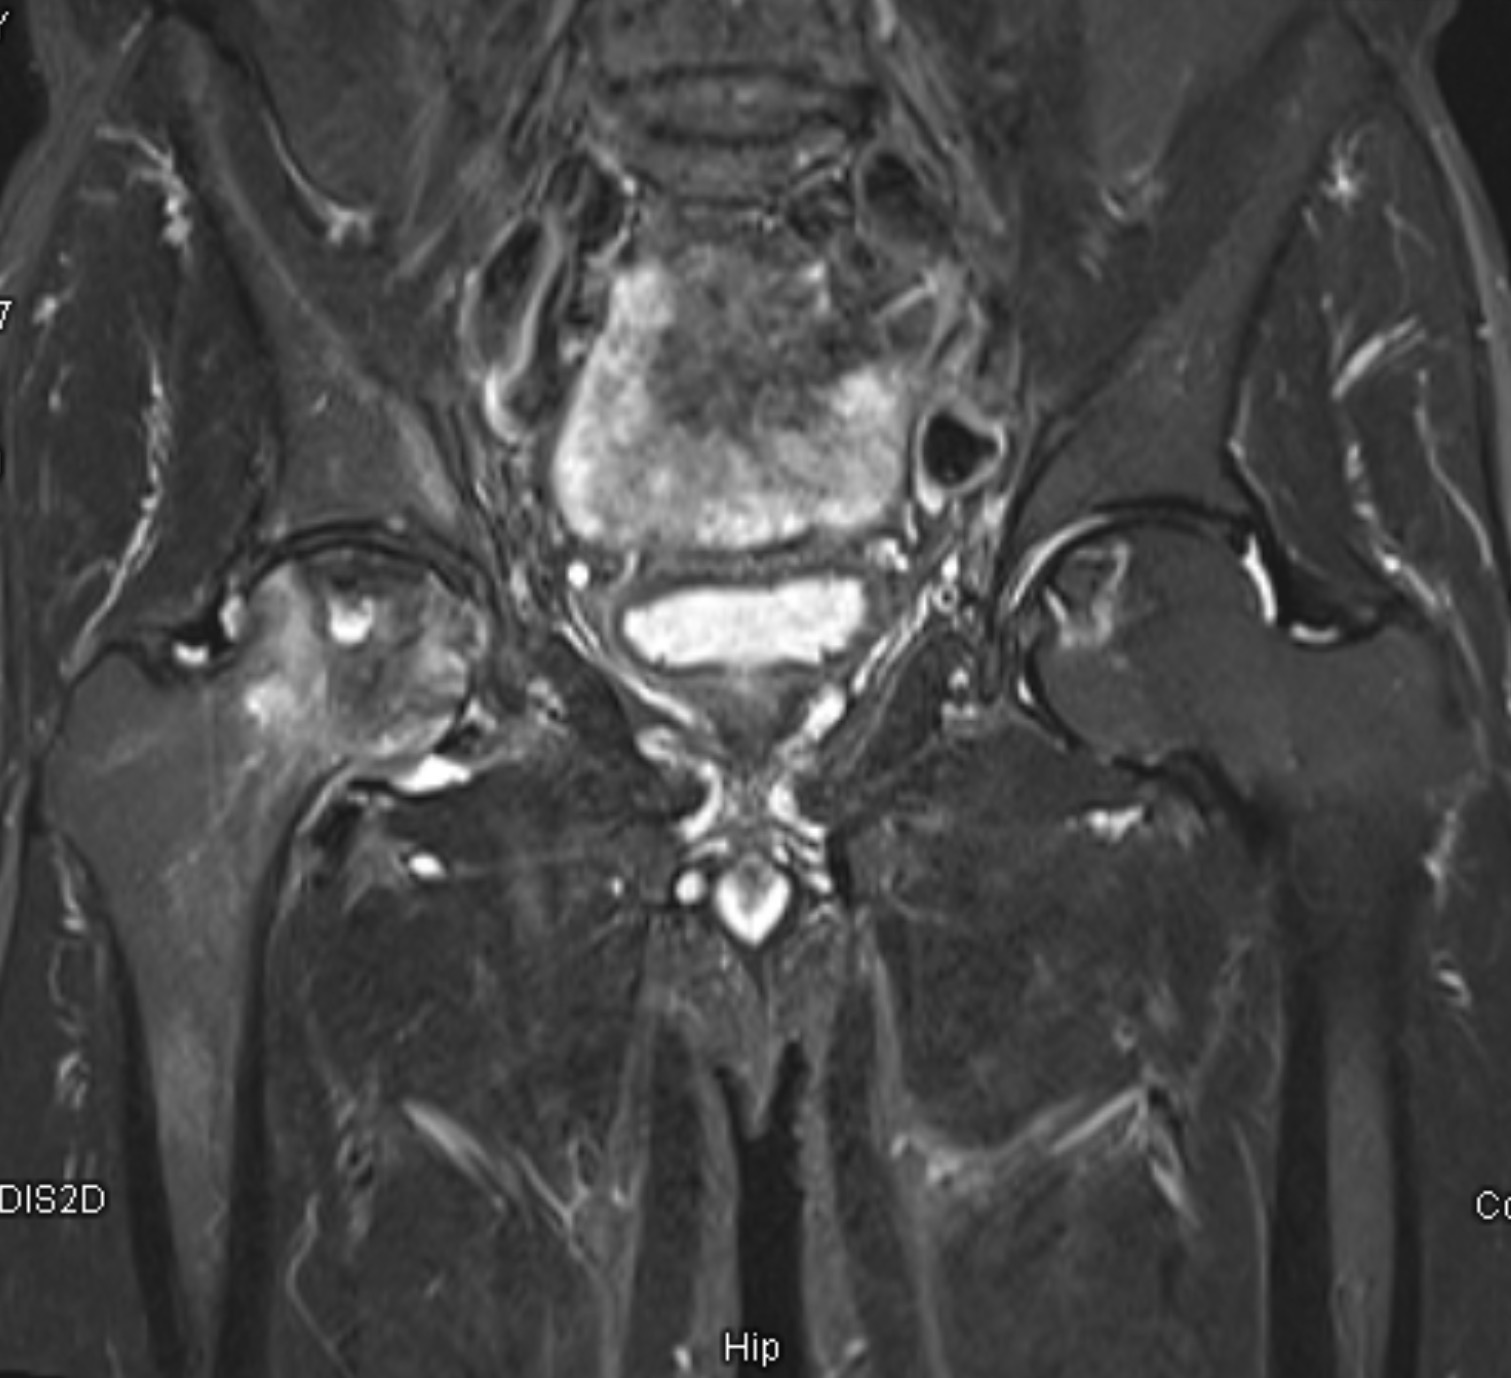

หลังทำ MRI พบว่าเขามี AVN ทั้งสองข้าง โดยข้างขวามีการยุบของหัวกระดูกชัดเจน (เริ่มเสียรูป) ส่วนข้างซ้ายเป็นระยะเริ่มต้น

✔ 3) MRI (สำคัญที่สุด)

เป็นการตรวจที่ละเอียดที่สุด เห็นการขาดเลือดของหัวกระดูกตั้งแต่ระยะเริ่มต้น ก่อนมีการยุบตัว

หมอจะใช้ผล MRI เพื่อแบ่งระยะของโรค เช่น Ficat stage ซึ่งช่วยกำหนดแนวทางการรักษา